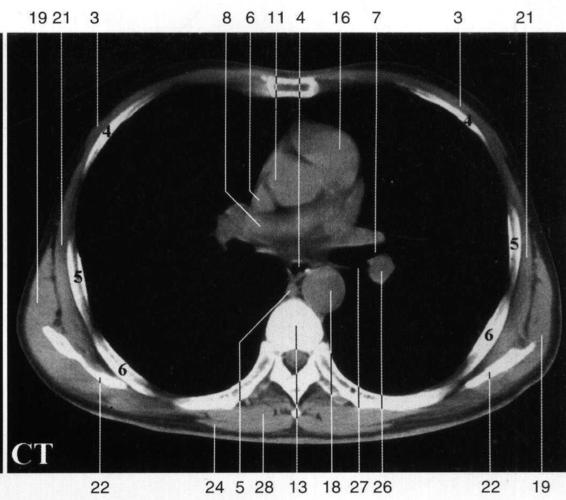

竖脊肌 erector spinae s Ⅲ